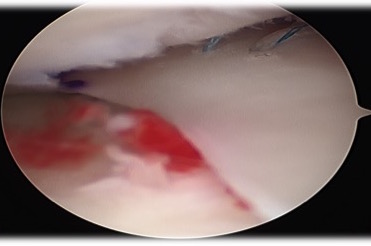

- place suture at junction of body and posterior horn

- make posteromedial approach

- secure posterior horn with all inside sutures, body with inside out, anterior horn with outside in